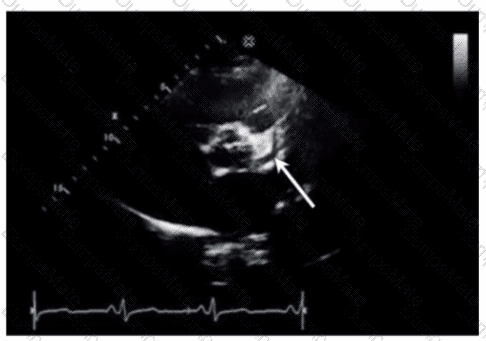

Questions 39

Which wall is indicated by the arrow on this video?

AE-Adult-Echocardiography Question 39

Options:

A.

Anteroseptum

B.

Anterolateral

C.

Inferoseptum

D.

Inferolateral